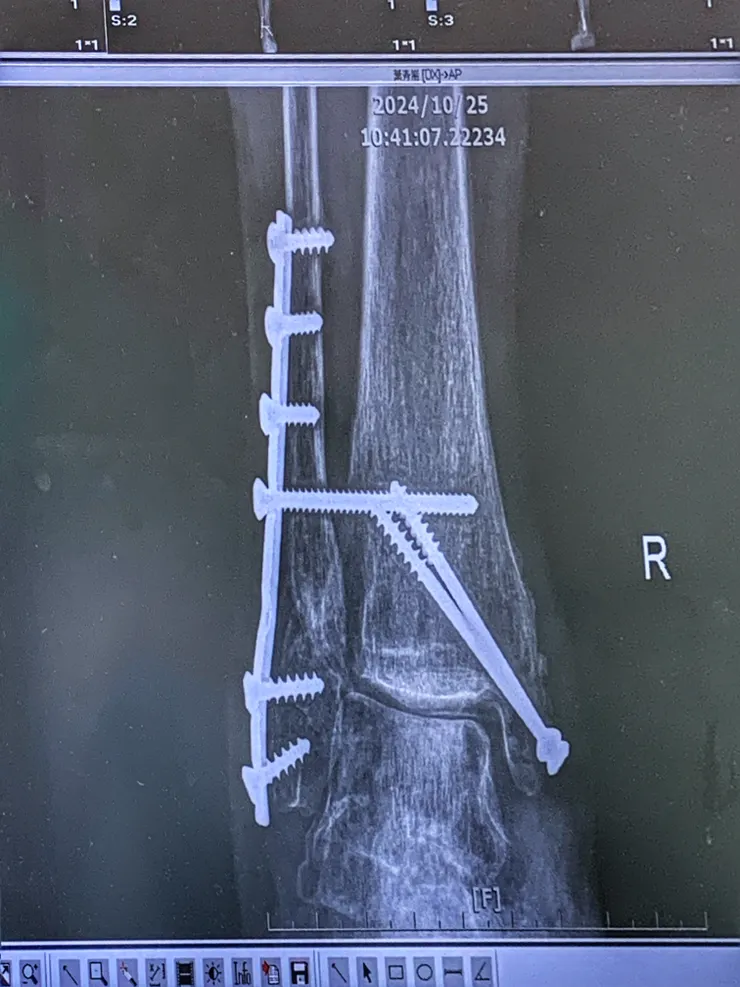

2024年7月30骨折手術,打了一支鋼片兩隻鋼釘